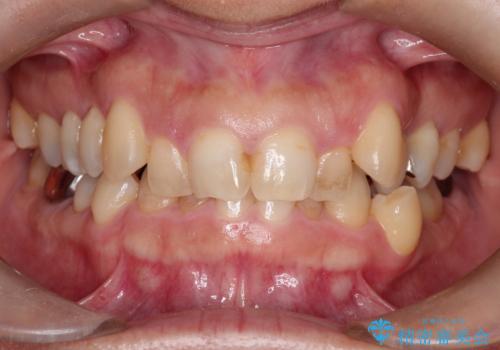

【審美装置】前歯のがたがたを治したい

- 前歯の凸凹と口元の突出感を主訴に来院されました。

臼歯関係が上顎前突傾向のため、上の小臼歯を抜歯してワイヤー矯正を行なっております。

下顎の叢生はIPRを行なって配列しています。